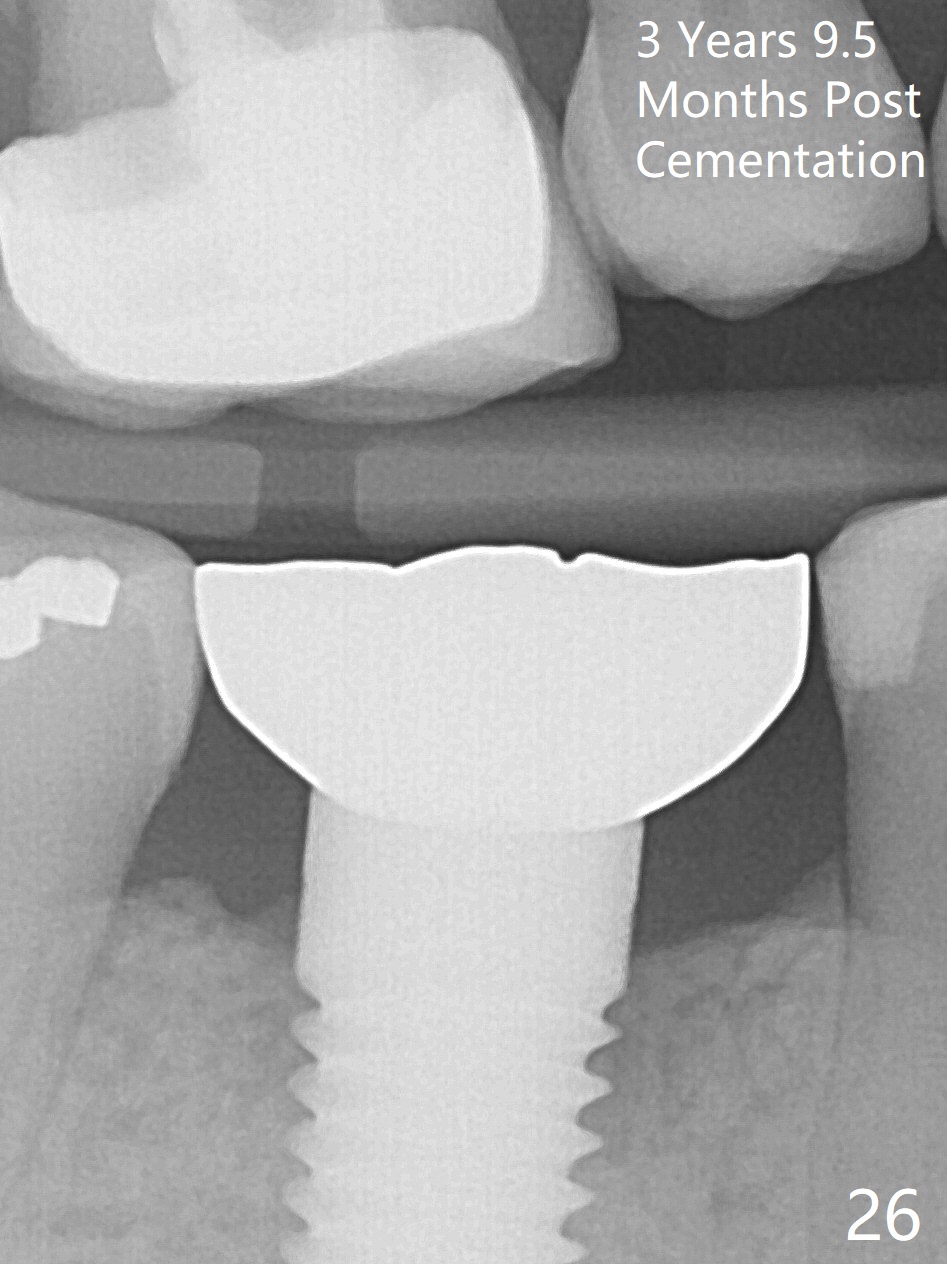

The patient will return for immediate implant at #14. Do not forget placing an implant as palatal as possible. There is no sign of infection at #30 three years 9.5 months post cementation because of water pik for #3 endo failure (Fig.25,26).